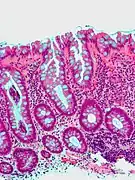

| Hyperplastic polyp | Colorectal (unless otherwise specified) | Serrated unbranched crypts | if polyps are more than 100 |  |

Serrated polyposis syndrome |

| Hyperplastic polyp of the stomach | Stomach | Elongated, tortuous, and cystic foveolae separated by edematous and inflamed stroma.[4] |  |

Gastric hyperplastic polyposis | |